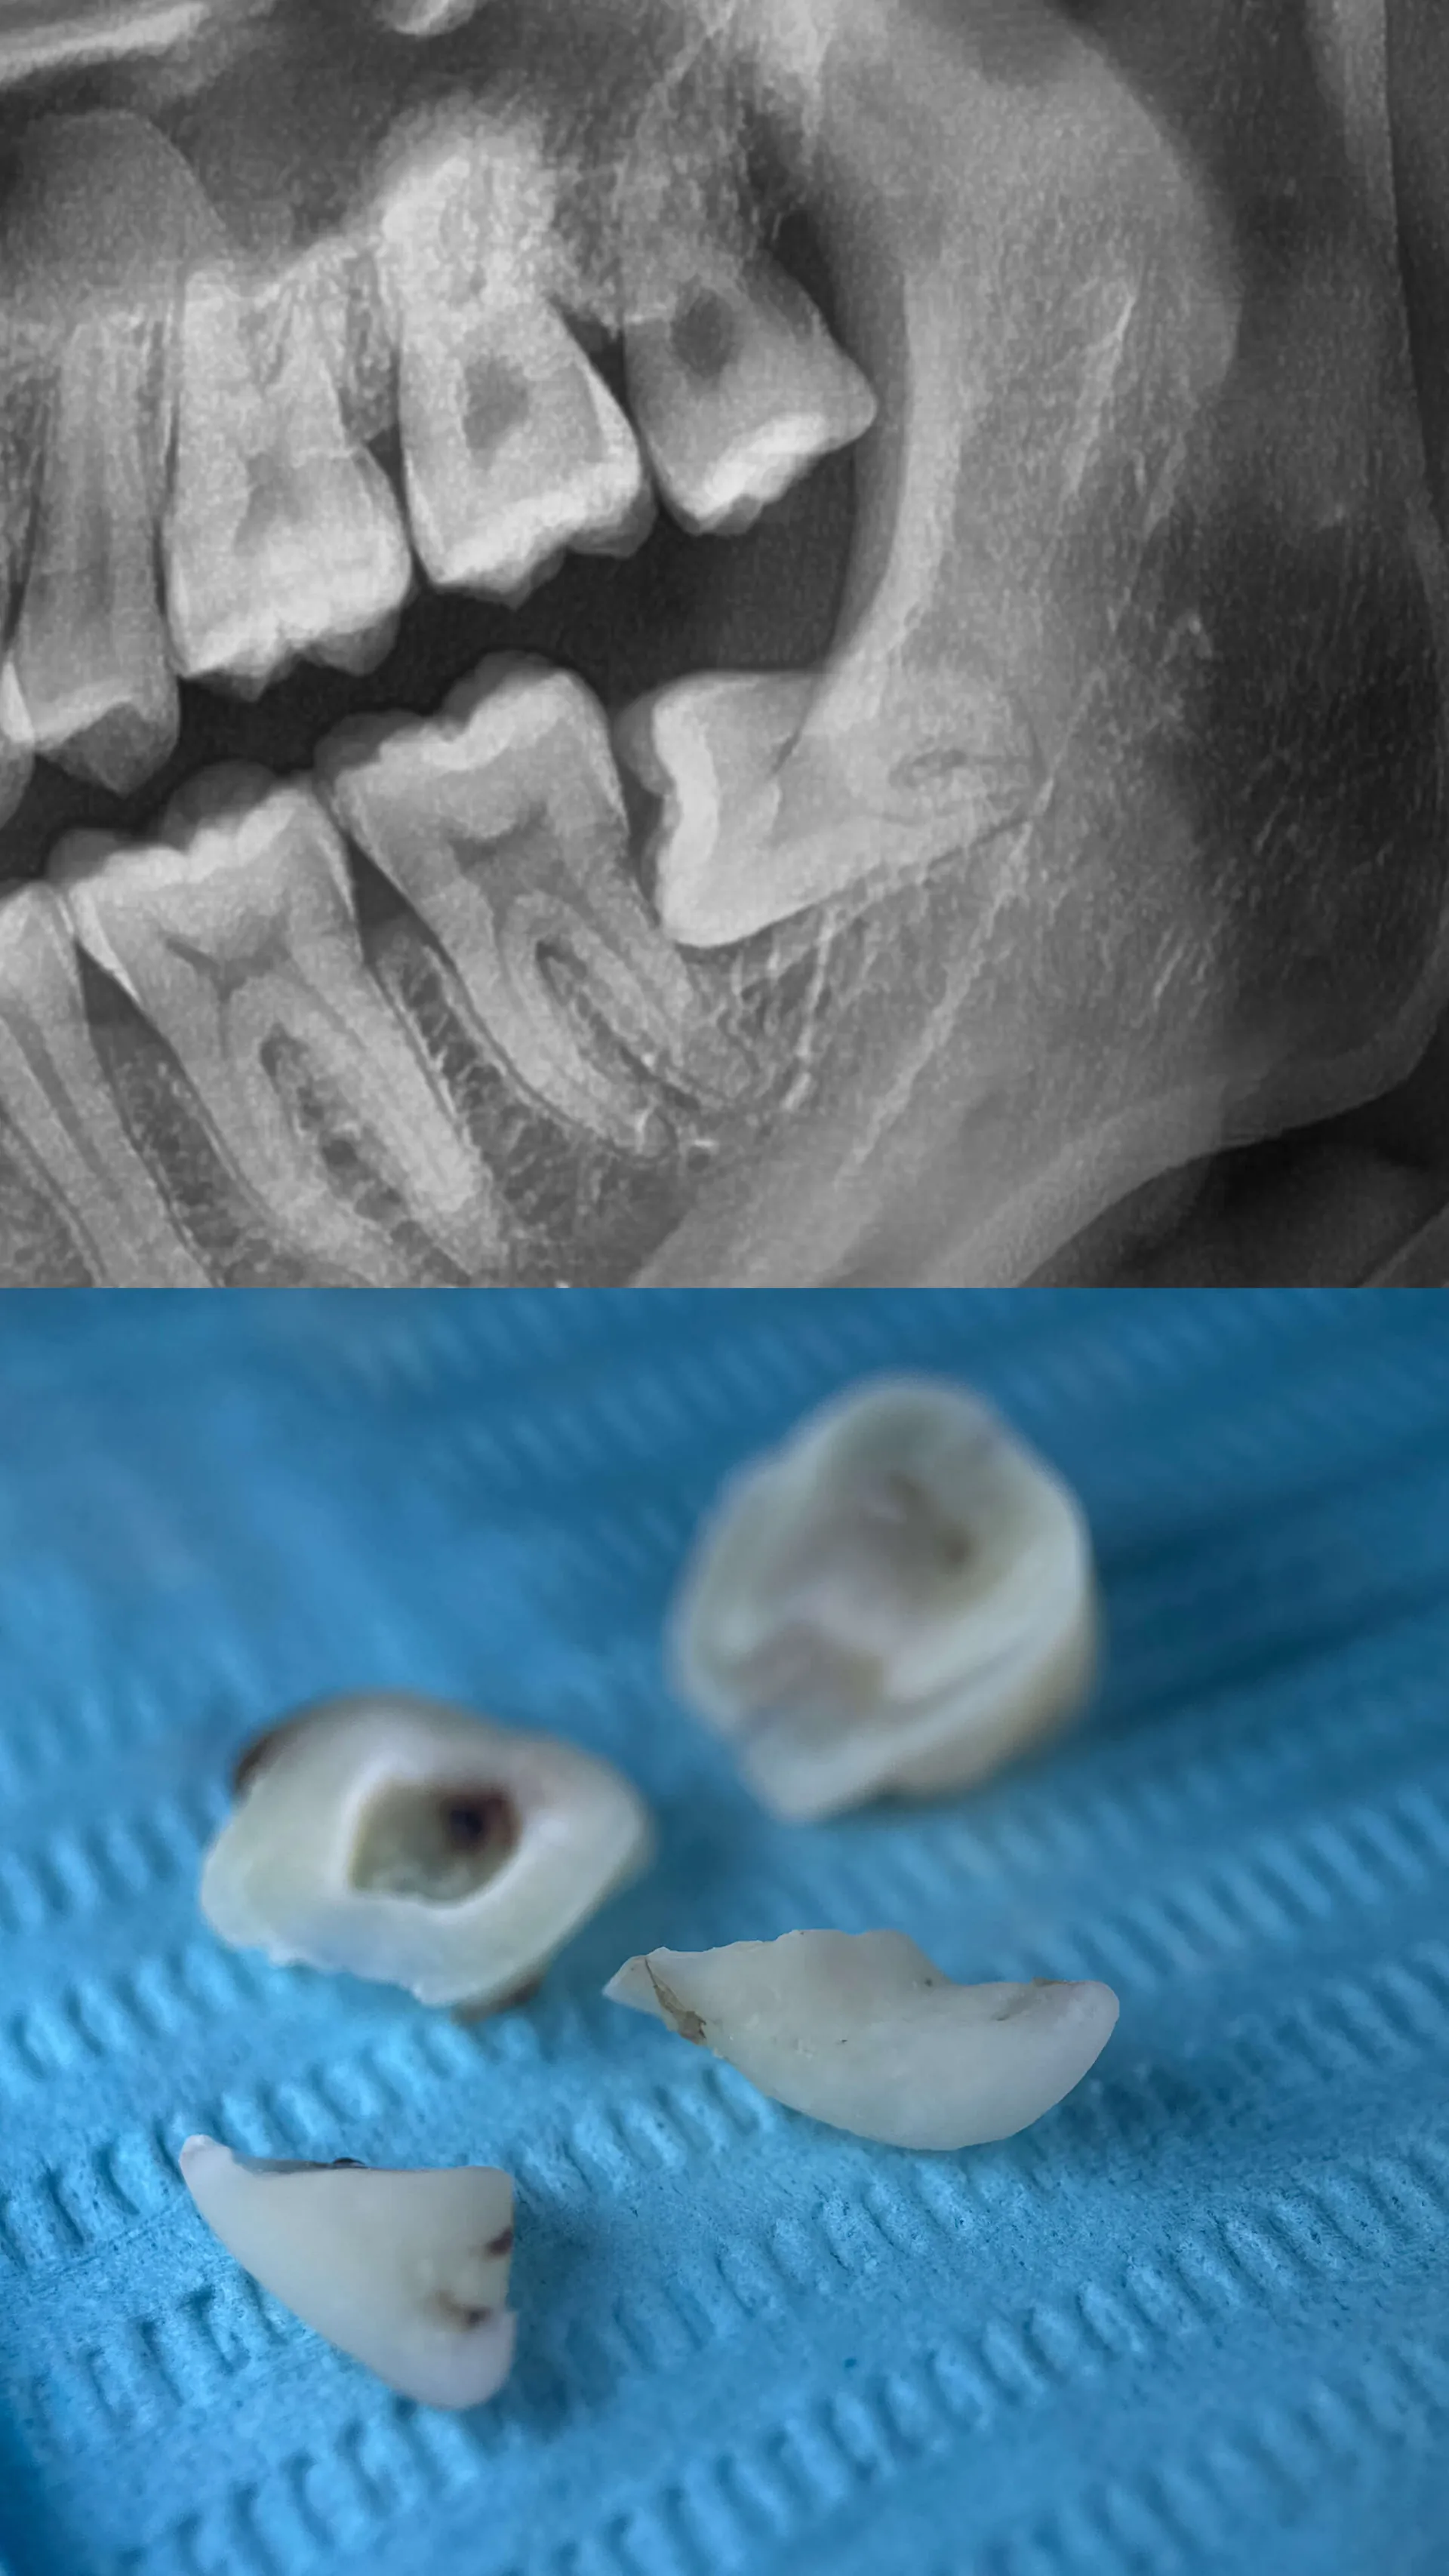

Wisdom Teeth Surgery

Choose us for painless and comfortable wisdom teeth removal because we're experts who prioritize your well-being. Our skilled team uses advanced techniques to ensure a smooth and efficient procedure. Trust us to provide a stress-free and compassionate experience while taking care of your wisdom teeth.